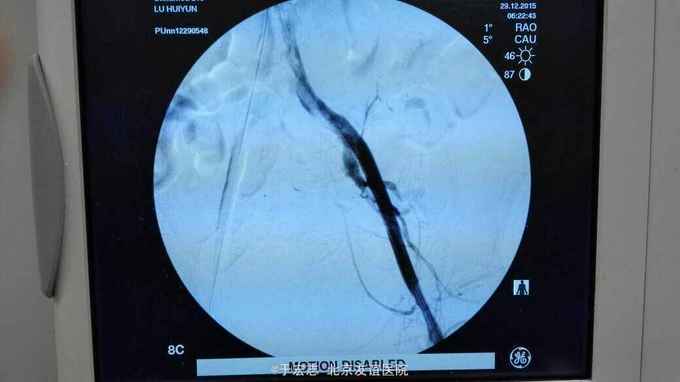

全腔内技术操作,用8F rotarex机械取栓导管操作,术前留置股静脉鞘,边操作边放静脉血,减少毒素吸收。静脉血经自体血回收处理。 操作完成后以血管缝合器缝合股动脉穿刺点,加压包扎。 患者转重症医学科途中出现心跳骤停,于手术室心外按压2小时复苏成功,转重症医学科血滤治疗。术后五小时生命体征均可维持,但家属还是放弃进一步治疗转运回当地治疗。